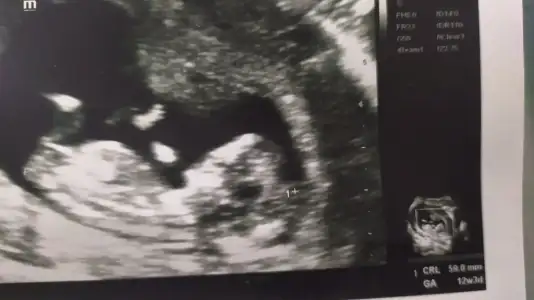

Kız görünüyorIkra meyra 12+4 canm

Tsk ederm canm önceki fotolarda erkek demistin ama sorun yok 1 ay sonra öğrenince oylayacagim anketiniKız görünüyor![]()

Önceki usg kaç haftalık bu kaç haftalik önceki daha net ise erkektir 11 12 13 haftalar olmalıTsk ederm canm önceki fotolarda erkek demistin ama sorun yok 1 ay sonra öğrenince oylayacagim anketini![]()

Bana göre hiçbiri net değilÖnceki usg kaç haftalık bu kaç haftalik önceki daha net ise erkektir 11 12 13 haftalar olmalı

Ikra meyra gecen sene kizimi tahminde dogru bilmistin canim 13+3haftalik gebeyim tekrardan var mi bi tahminin